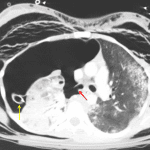

- Complete avulsion of the right mainstem bronchus with near complete collapse of the right lung dependently within the right thoracic cavity

- Large right pneumothorax with leftward mediastinal shift and a right thoracostomy tube terminating in the right apex

- Extensive consolidation with scattered pneumatocele formation in the right lung

Complete avulsion of the right mainstem bronchus with a resultant large right pneumothorax and near complete collapse of the right lung.

Persistent leftward mediastinal shift despite placement of a large bore right thoracostomy tube.

Small, infiltrating mediastinal hematoma, likely related to the bronchial avulsion.